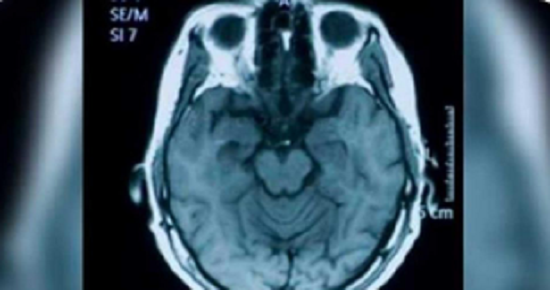

Jest to badanie, które doprowadziło do niesamowitego wniosku. Okazuje się, że posiadanie słabej pamięci nie musi być czymś negatywnym.

Zapominanie może być oznaką bardzo wysokiej inteligencji. Myśleliśmy, że jest odwrotnie, a jednak – pozory mylą!

Mózg inteligentnej osoby puszcza rzeczy, których już nie potrzebuje, co ułatwia myślenie i podejmowanie decyzji.